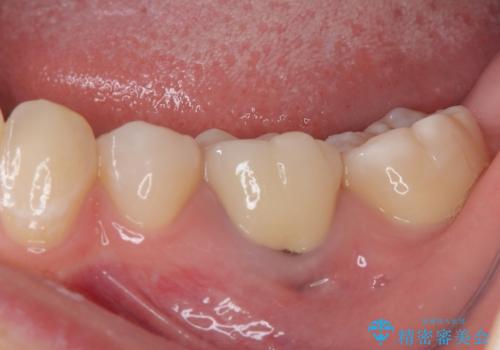

- 神経を取り除いた後に歯の色が変色して気になってきたとのことで来院された患者様です。

前歯は片側のみ神経を取り除かれていましたが、反対側もむし歯治療の詰め物が広範囲に及んでいたため、両方の歯をオールセラミッククラウンにて補綴治療を行うこととしました。

奥歯も著しく茶色に変色していたため、同様にオールセラミッククラウンにて補綴治療を行うこととしました。